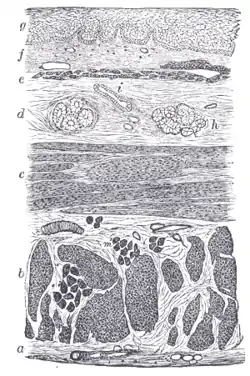

Section of the human esophagus. Moderately magnified.

Section of the human esophagus. Moderately magnified. Section of mucous membrane of human stomach, near the cardiac orifice.